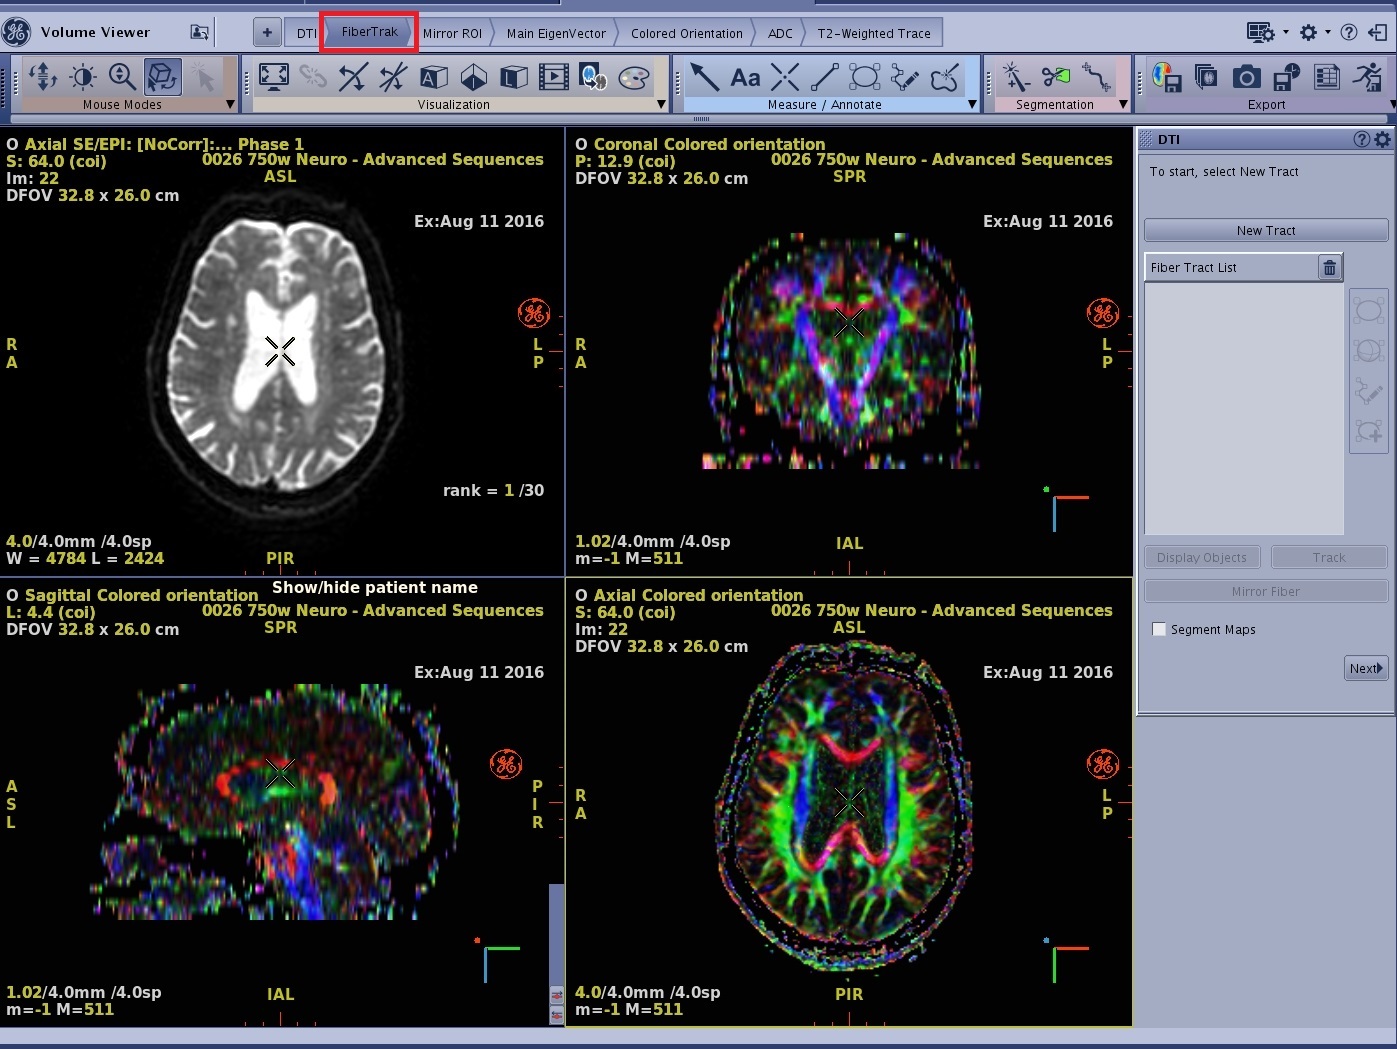

- The DTI protocol is launched. All selected series are displayed in the Review Steps. DTI, FiberTrak, Mirror ROI, Main EigenVector, Colored Orientation, ADC and T2-Weighted Trace are always displayed with the DTI protocol. Other series displayed in the Review Steps are dependent on the series selected from the Patient List.

- From the Review Steps, click FiberTrak.

- The coronal, sagittal and axial viewports are displayed as Colored orientation maps.

Figure 3. FiberTrak review step selected